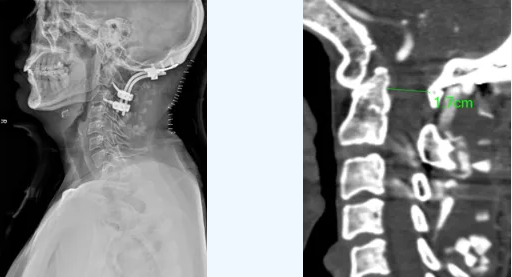

近日,郑州大学第五附属医院骨科二病区成功开展一例高难度的后入路寰枢椎复位钉棒内固定术,顺利解除了患者高位颈髓的严重压迫。

三维手术规划:利用CT血管成像进行三维重建,精确描绘椎动脉异常走行路径,为每一颗螺钉规划出安全的“植入通道”。

在神经电生理监测与术中全程透视的“双重护航”下,手术团队凭借丰富经验,于解剖结构复杂的“危险区域”精准操作,成功置入全部螺钉,未损伤椎动脉。随后利用钉棒系统,安全、有效地对脱位的寰枢椎进行复位,并植入人工骨实现永久性稳定融合。